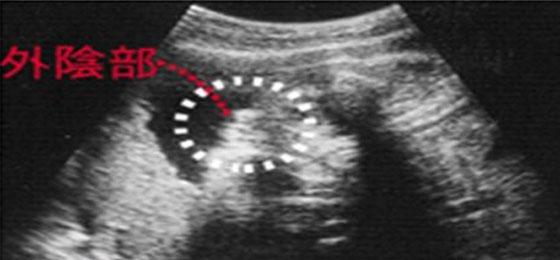

女宝宝四维彩超图

三条白线是较着的女宝特征,若是没有看到较着的三条白线,就看两腿之间有没有凸起的东东,且中心有小凹槽的,就是女宝